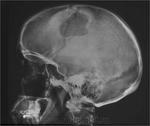

мужчиа 42 года рождения. находится в реанимации с диагнозом ОНМК с правосторонним гемипарезом, повторон. в анамнезе комбинированный митральный порок сердца. Что это такое в височно теменной области слева, энхондрома?  метастаз? на рентгеннограмме ОГК расширен правый корень (центральный рак?) и круглая тень в левом легочном поле (метастаз?). какие будут предположения? в анализах ничего особенного ни СОЭ повышенного ни лейкоцитоза. можно было бы ЛТГ сделать но рентгенаппарат сломался (сгорели инверторы) - так что томки врят ли ожидаются в близжайшее время.

На снимках черепа ничего патологического, особенности строения костей черепа. В легких( на снимке четко видно слово "лЁжа") м. предположить пневмонические, застойные дела, порок сердца, ревматические - или возрастные проблемы. Затемнение в в/д справа - возможна и "инфаркт- пневмония". Корень расширен- скорее, не к онкологии, а к сердечным проблемам.

В черепе тоже не метастазы.

Почему не метастазы?. Они с относительно четким контуром бывают. Тут в теменной кости участок, и похоже что не один, в лобной кости, затылочная тоже вопросы вызывает.. Не знаю как стрелку нарисовать, но в одном участке если присмотреться тонкие спикулы - периостальная реакция..

1. И все равно придумываете. 2. Эта картина похожа на гемангиому (что и показал Валентин Львович). 3 Как бы вам объяснить? Короче, была бы шишка при метастазе таких размеров.

Все поняла, глупость написала - смутил рваный вид костей черепа, а это просто видимо из-за укладки шов так получился

укладка не правильная, все в этом дело. лаборанты ленятся ровно положить и проконтролировать чтоб не двигал после.

Гемангиома. Типичная локализация в области теменного бугра, гладкий, четкий контур, фестончастые края, намечающаяся звездчатая структура. Все типично. Хрящевых опухолей в костях свода не бывает. Там нет хряща.